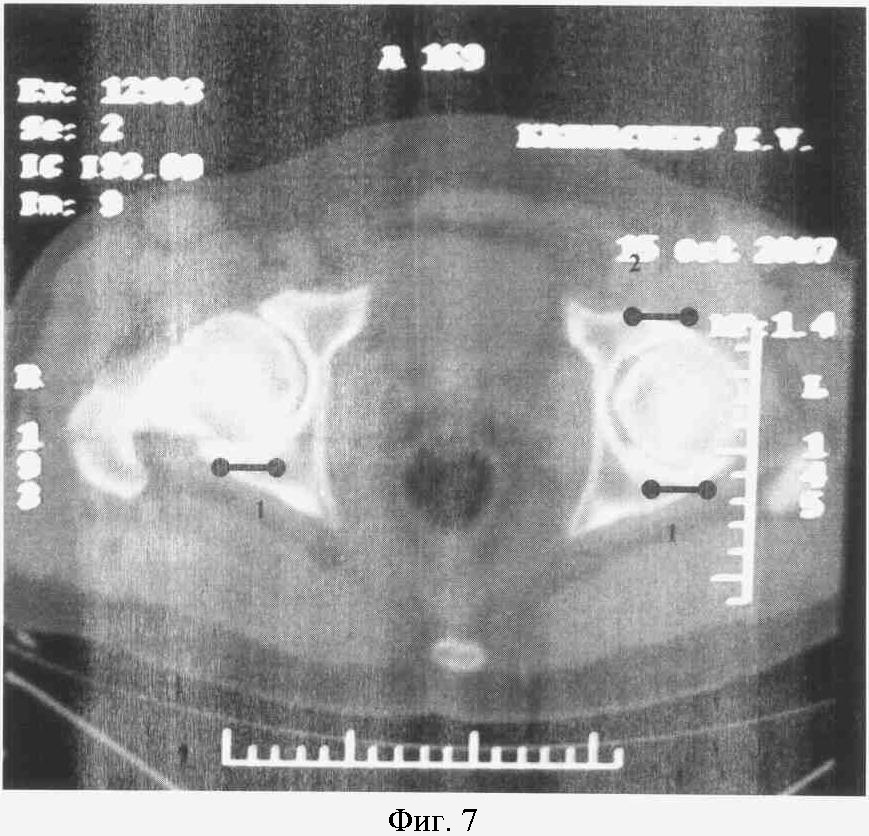

На фиг.7. представлен КТ срез на уровне нижней трети головки бедра больного К.

Справа: 1-я стадия коксартроза с локализацией участков компрессии в заднем отделе сустава (1).

Слева: 2-я стадия коксартроза с кистевидной перестройкой с локализацией участков компрессии в заднем (1) и переднем отделах сустава (2).